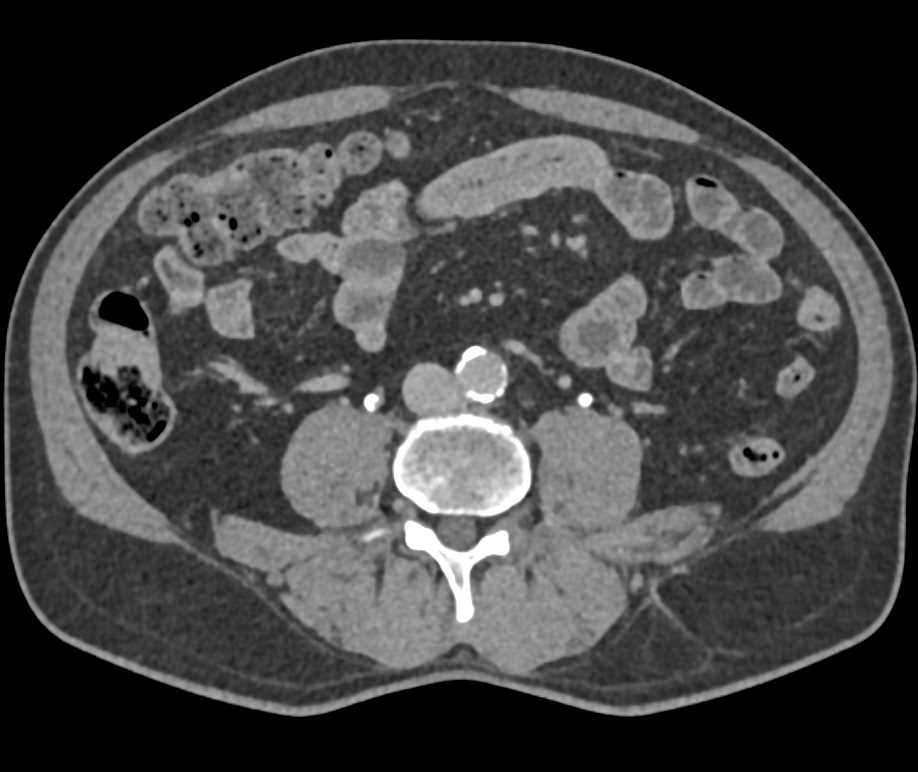

Transitional Cell Carcinoma Right Kidney and Bladder